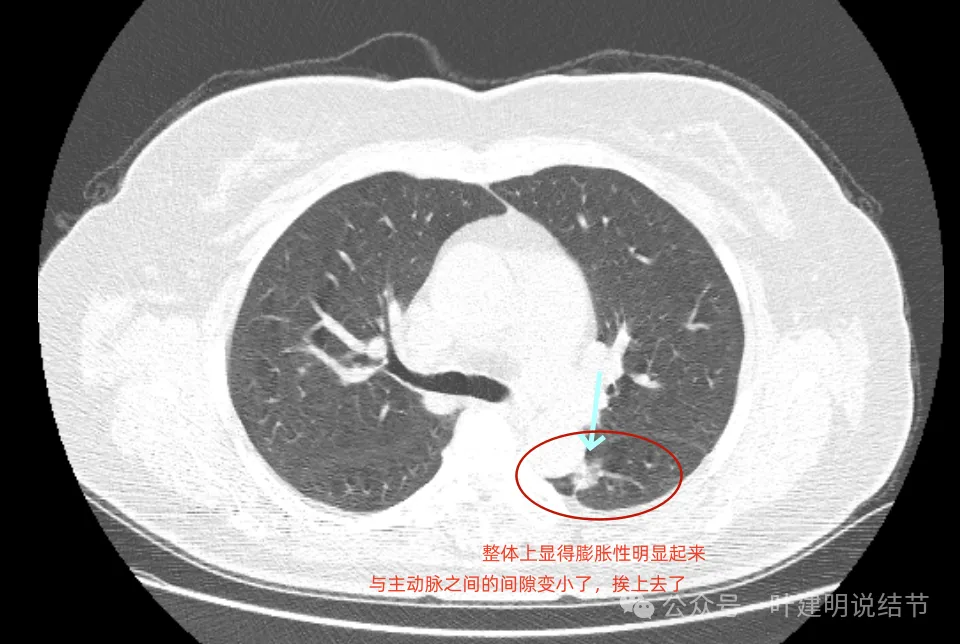

再看2022年的影像:

病灶磨玻璃密度,天蓝色这处密度高的条索状,紫色这处毛刺细长,病灶此层没有膨胀性,更像慢性炎伴纤维增生的样子。

密度不均,有实性成分了,表面分叶,但膨胀性仍不强。

基本实性密度,边缘较为平直,胸膜牵拉不显著。

病灶瘤肺边界稍显模糊,但与2019年时比,邻近胸膜增厚似乎不如之前明显。

从3年对比来看,由于没有吸收好转,也说不上显著展,虽恶性概率较前有所增加,但慢性炎或肉芽肿性炎仍可能的。谨慎随访也是可行的。当然现灶在边缘,若定要明确,微创手术也是可行的。或者查下PET,但这种几乎进展不明显的病灶,估计有代谢增高,一般也是轻度增高,仍不能完全明确性质的。

病灶膨胀感较之前明显;与主动脉壁之间缝隙不太明显了。